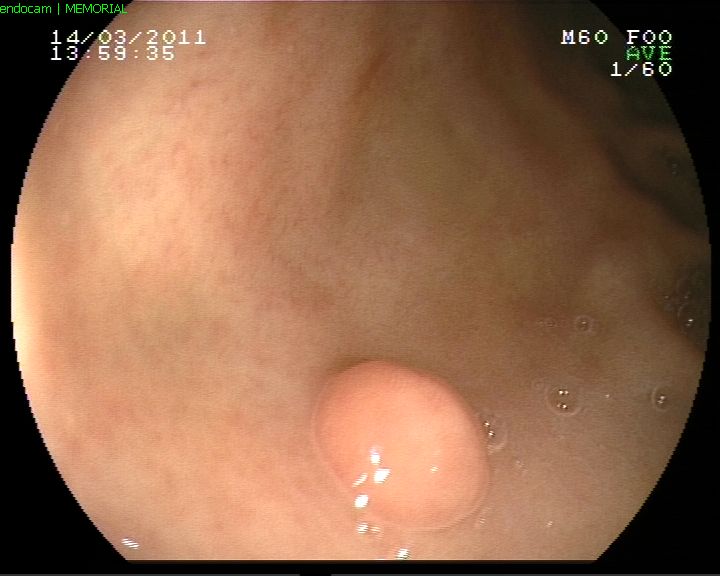

Midede polip